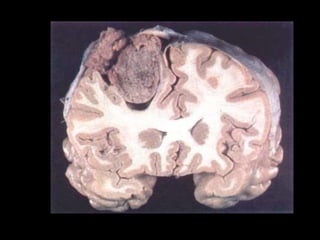

Gross

• Globular, encapsulated tumors

• Attached to dura & compress the underlying brain

without invasion

• Are usually easily separated from pia

• May occur as a flattened sheath of tumor, taking

the shape of the under lying bone, meningioma en

plaque more common in the area of the sphenoid

bone

• Cut surface pale & translucent or homogenous &

reddish-brown, depending on the degree of

vascularity

• Gritty in consistency

• Cut surface has a whorled pattern after fixation

• Intratumoral hemorrhage is rare, & necrosis is

generally absent (occurs with malignant

degeneration)